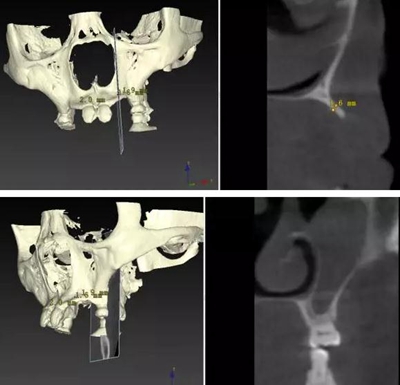

??茩z查:口內(nèi)僅剩16,11,21,26,雙側(cè)上下頜乳牙E滯留,其余恒牙缺失,上下頜骨發(fā)育不足,缺牙區(qū)牙槽嵴呈刃狀,上下頜弓比例協(xié)調(diào)。CBCT顯示:上頜前牙區(qū)牙槽嵴寬度約2-3mm,骨高度約10mm;上頜后牙區(qū)可用牙槽骨高度僅1-2mm,左右側(cè)上頜

竇內(nèi)粘膜有明顯增厚。下頜牙槽骨寬度及高度嚴(yán)重不足,僅存有基骨。

由于牙槽骨寬度嚴(yán)重不足,短種植體不適用于此類患者。因此,上述病例屬于難度極高的種植對象,讓很多種植醫(yī)生一籌莫展。

顴種植手術(shù)可以有效縮短該病例的治療周期,實(shí)現(xiàn)患者固定義齒修復(fù)的愿望。如果手術(shù)順利,患者有望在較短時間內(nèi)完成整個修復(fù)治療,恢復(fù)正常青年人的牙列狀態(tài)和外形,獲得自信,提高生活質(zhì)量。由于患者家境貧寒,種植手術(shù)材料費(fèi)用較高,目